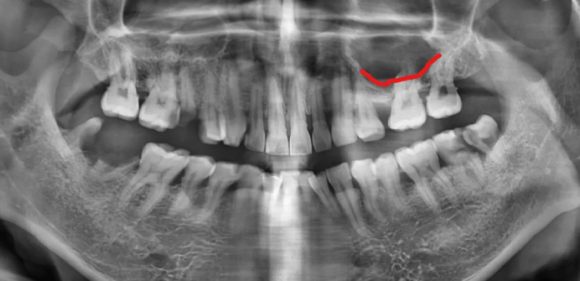

2024.02.13 초진 파노라마, (사진상 좌.우 반대)

- 충치 문제: 오른쪽 어금니(사진상 왼쪽)는 뿌리까지 충치가 심해 발치가 필요한 상태였습니다.

- 잇몸뼈 부족: 왼쪽 위 어금니(사진상 오른쪽)는 이 뽑은 후 잇몸뼈가 1~2mm밖에 남지 않을 것으로 예상되었는데요.

이 경우 임플란트 고정이 어렵기 때문에 뼈 이식과 상악동 거상술이 필요했습니다.

- 교합 불안정: 치아가 빠진 자리를 오랫동안 방치해 배열이 틀어지면서 치아 맞물림 상태가 매우 불안정해졌습니다.

먼저, 충치가 심한 어금니는 발치 후 임플란트를 하기로 결정했는데요.

자연치아를 살리는 것을 우선으로 하지만, 뿌리만 남거나 염증이 심한 경우 주변 치아를 위해 발치를 하는 것이 더 좋은 결과를 만들 수 있습니다.

또한 왼쪽 위 어금니는 발치 후 잇몸뼈가 부족뿐만 아니라, 상악동이라는 공기주머니와 가까운 위치에 있어 측면 접근법 상악동 거상술이라는 난도 높은 수술과 임플란트 골이식이 필요했는데요.

빨간선이 상악동 위치